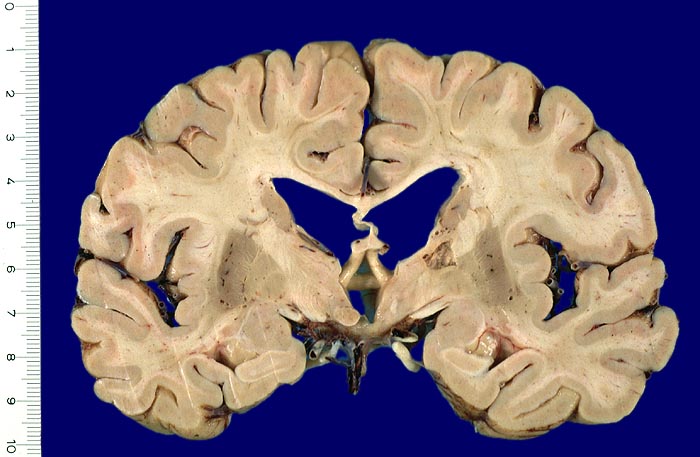

Lakunäre Infarkte im Bereich des Linsenkerns, des Thalamus, der Capsula interna, der tiefen weissen Substanz, des Nucleus caudatus und der Pons sind weniger als 1.5cm gross und oft Folge einer hypertensiven Enzephalopathie (Atherosklerose der Arteriolen, welche Basalganglien, weisse Substanz und Hirnstamm versorgen). Das Vorliegen multipler Lakunen wird als Status lacunaris bezeichnet. Die Infarkte sind je nach Lokalisation symptomatisch oder asymptomatisch.